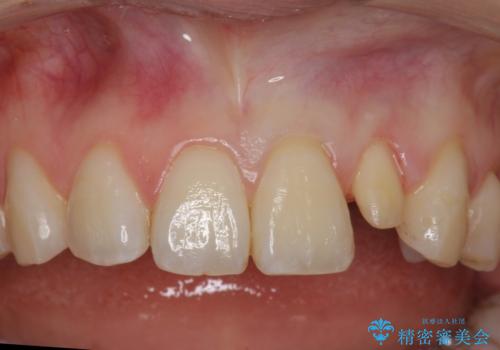

- 左上の前歯が生まれつき小さく、前に飛び出していました。

矯正治療で引っ込めてから、形を左右対称に整えるセラミック治療を行いました。